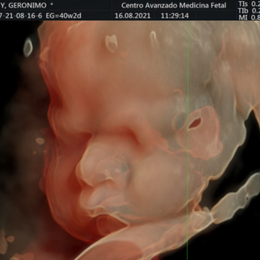

Ecografía del corazón fetal en 4D

- Las formas nuevas de ecografía pueden proporcionar imágenes en 5-D.